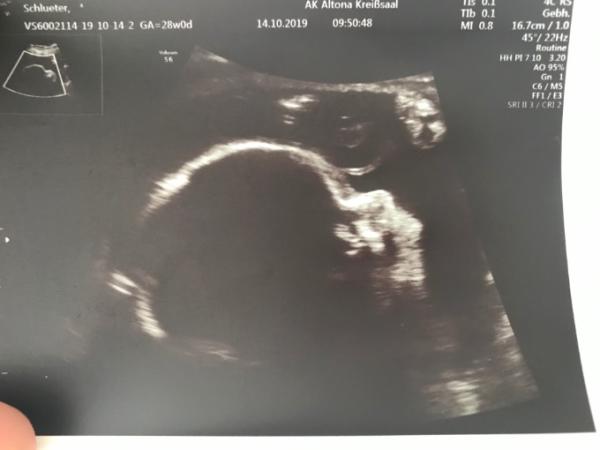

Huhu. Ich war gerade zum Geburtsplanungsgespräch im Krankenhaus. Durch meine Ss Diabetis und meinen vorherigen OP s an der Gebährmutter wird der kleine Mann bei 38+0 geholt. Das ist dann der 23.12.19.... bescheidenes Datum, aber gut, vielleicht kommt er ja doch früher. Meine Maus ist damals auch schon bei 36+5 ausgezogen Bin heute bei 28+0 und der kleine Mann wiegt ca. 1190 Gramm. Liegt auf der Patenzielle 44...!? Kann mir das jemand erklären! Danke Lg an alle

Bild zu Geplanter Kaiserschnitt am 23.12.19 - Forum für Januar - Mamis

Mal sehen, ob du dann damit die erste von uns bist Heute war mein Kollege mit seinem kleinen Mann da. Knapp drei Wochen alt. Wollte gar nicht, dass die wieder gehen. Muttergefühle sind da Super süßes Bild von deinem Mann :)